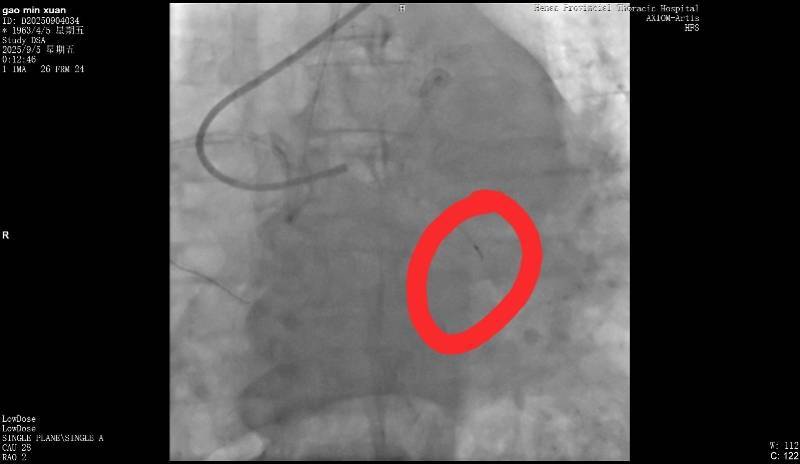

断裂的导丝皇冠信用网。受访者供图

9月5日,高女士父亲在该医院做冠脉造影,手术进行了近3个小时皇冠信用网。高女士回忆说,手术结束后,负责手术的医生告诉她,“在微创探查体内的时候,一截导丝断裂。”当高女士询问能否再次实施手术取出时,医生表示因病患年纪较大,开胸手术存在危险,并没有取出的必要。但对于遗留导丝会否在后续造成长期影响,该医生则称“无法确定”。

高女士提供的病程记录显示,“手术操作过程中出现回撤导丝困难,送入微导管尝试至坎顿处未成功,退出微导管时远段导丝断裂,多途径尝试取出断裂导丝均未能成功皇冠信用网。”资料还指出,“通过复查造影,回旋支近段残余狭窄小于30%,未见明显夹层、无复流。”

南都记者留意到,该病程记录给出了心血管外科一病区会诊意见,称“回旋支内见离断的介入导丝,外科取出导丝意义不大,建议内科治疗”皇冠信用网。